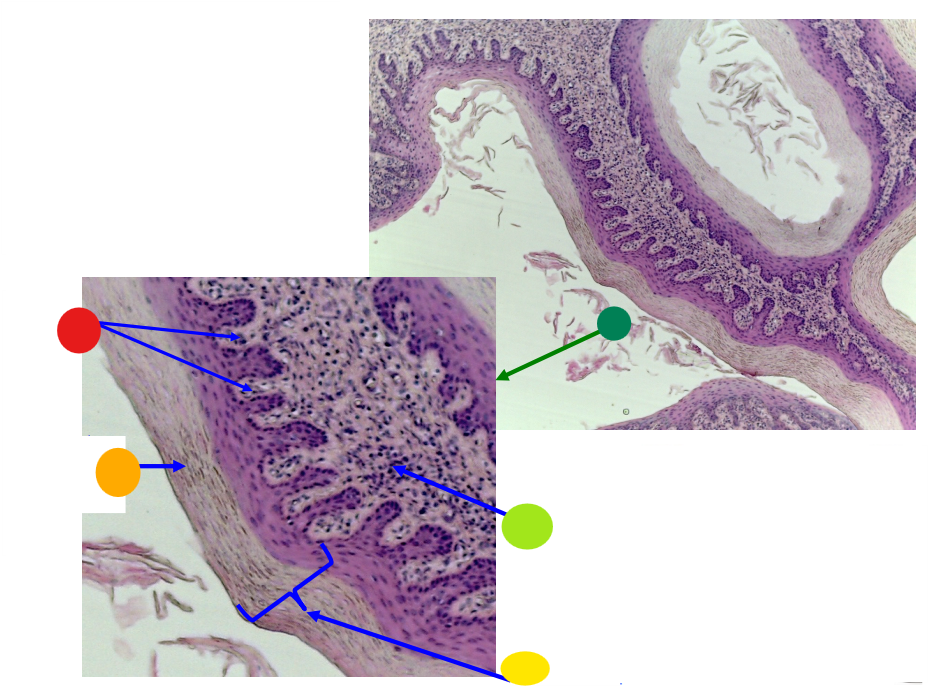

red

tunica albuginea

orange

primordial follicles

yellow

follicular cells

light green

primary oocyte

dark green

granulosa cells

light blue

primary follicles

what is this?

ovary

red

primordial follicles

red

primary follicles

red

tunica albuginea

orange

primary oocyte

yellow

primordial follicles

red

granulosa cells

orange

primary oocyte

what is this

primary follicle

red

tunica albuginea

orange

primordial follicles

red

primary follicle

orange

secondary follicles

what is this

tertiary follicle